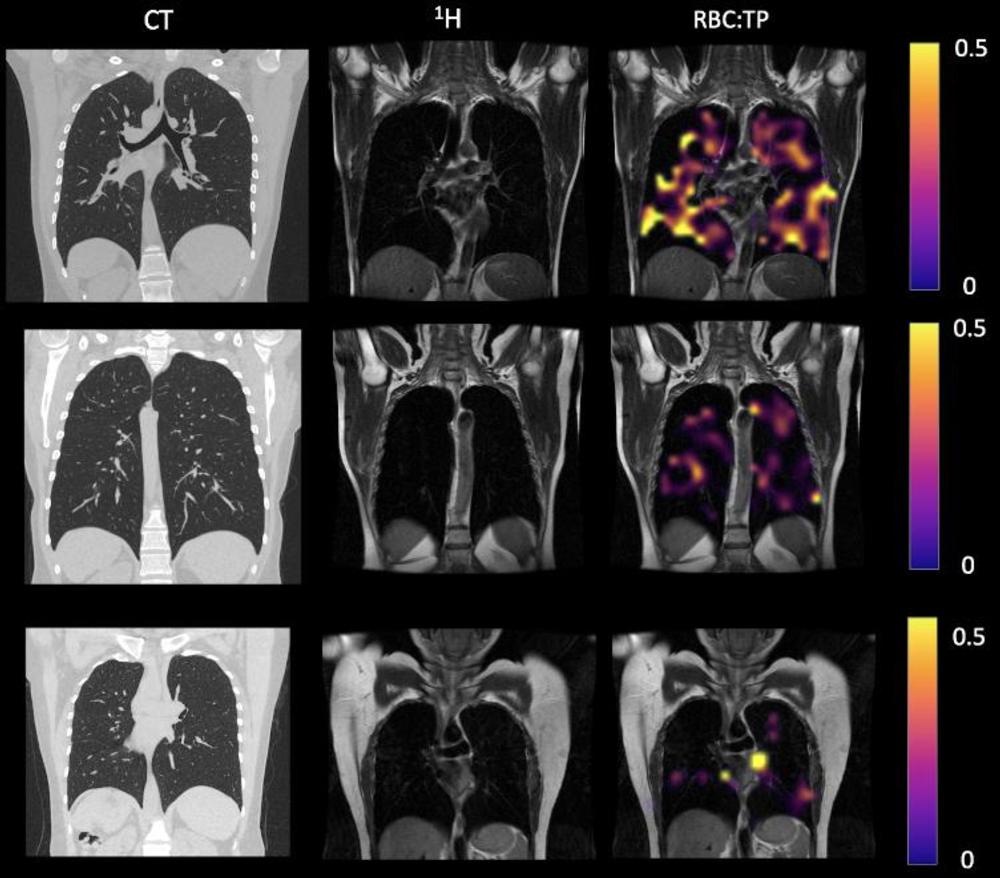

Figure 2. Example CT, proton, proton and RBC:TP imaging from post-Covid-19 condition participants. The top row is a participant with RBC:TP = 0.49, the middle row is a participant with RBC:TP of 0.31, and the bottom row is a participant with RBC:TP = 0.24. Imaging showed little to no discernible damage on CT, and yet highly heterogeneous and low RBC:TP in the lungs of non-hospitalized post-Covid-19 condition participants. RBC:TP = Hyperpolarized 129Xenon MRI lung ratio of red blood cell spectral peak to tissue phase spectral peak

High-res (TIF) version